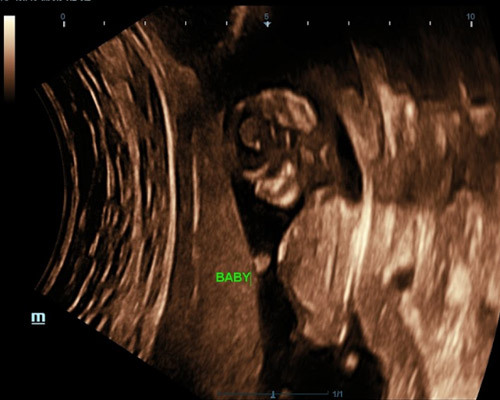

A viability scan near Wakefield is typically carried out between 6 - 12 weeks. It uses ultrasound imaging to assess how things are progressing in the early stages. During the appointment, the sonographer checks that the pregnancy is located correctly, looks for a visible heartbeat where possible, measures the embryo to estimate timing, and confirms whether there is one baby or more.

For many families, this type of early pregnancy scan Wakefield provides important reassurance. Seeing a heartbeat for the first time can be a meaningful moment and helps confirm that everything is developing as expected.

- A 2D ultrasound to confirm an intrauterine pregnancy